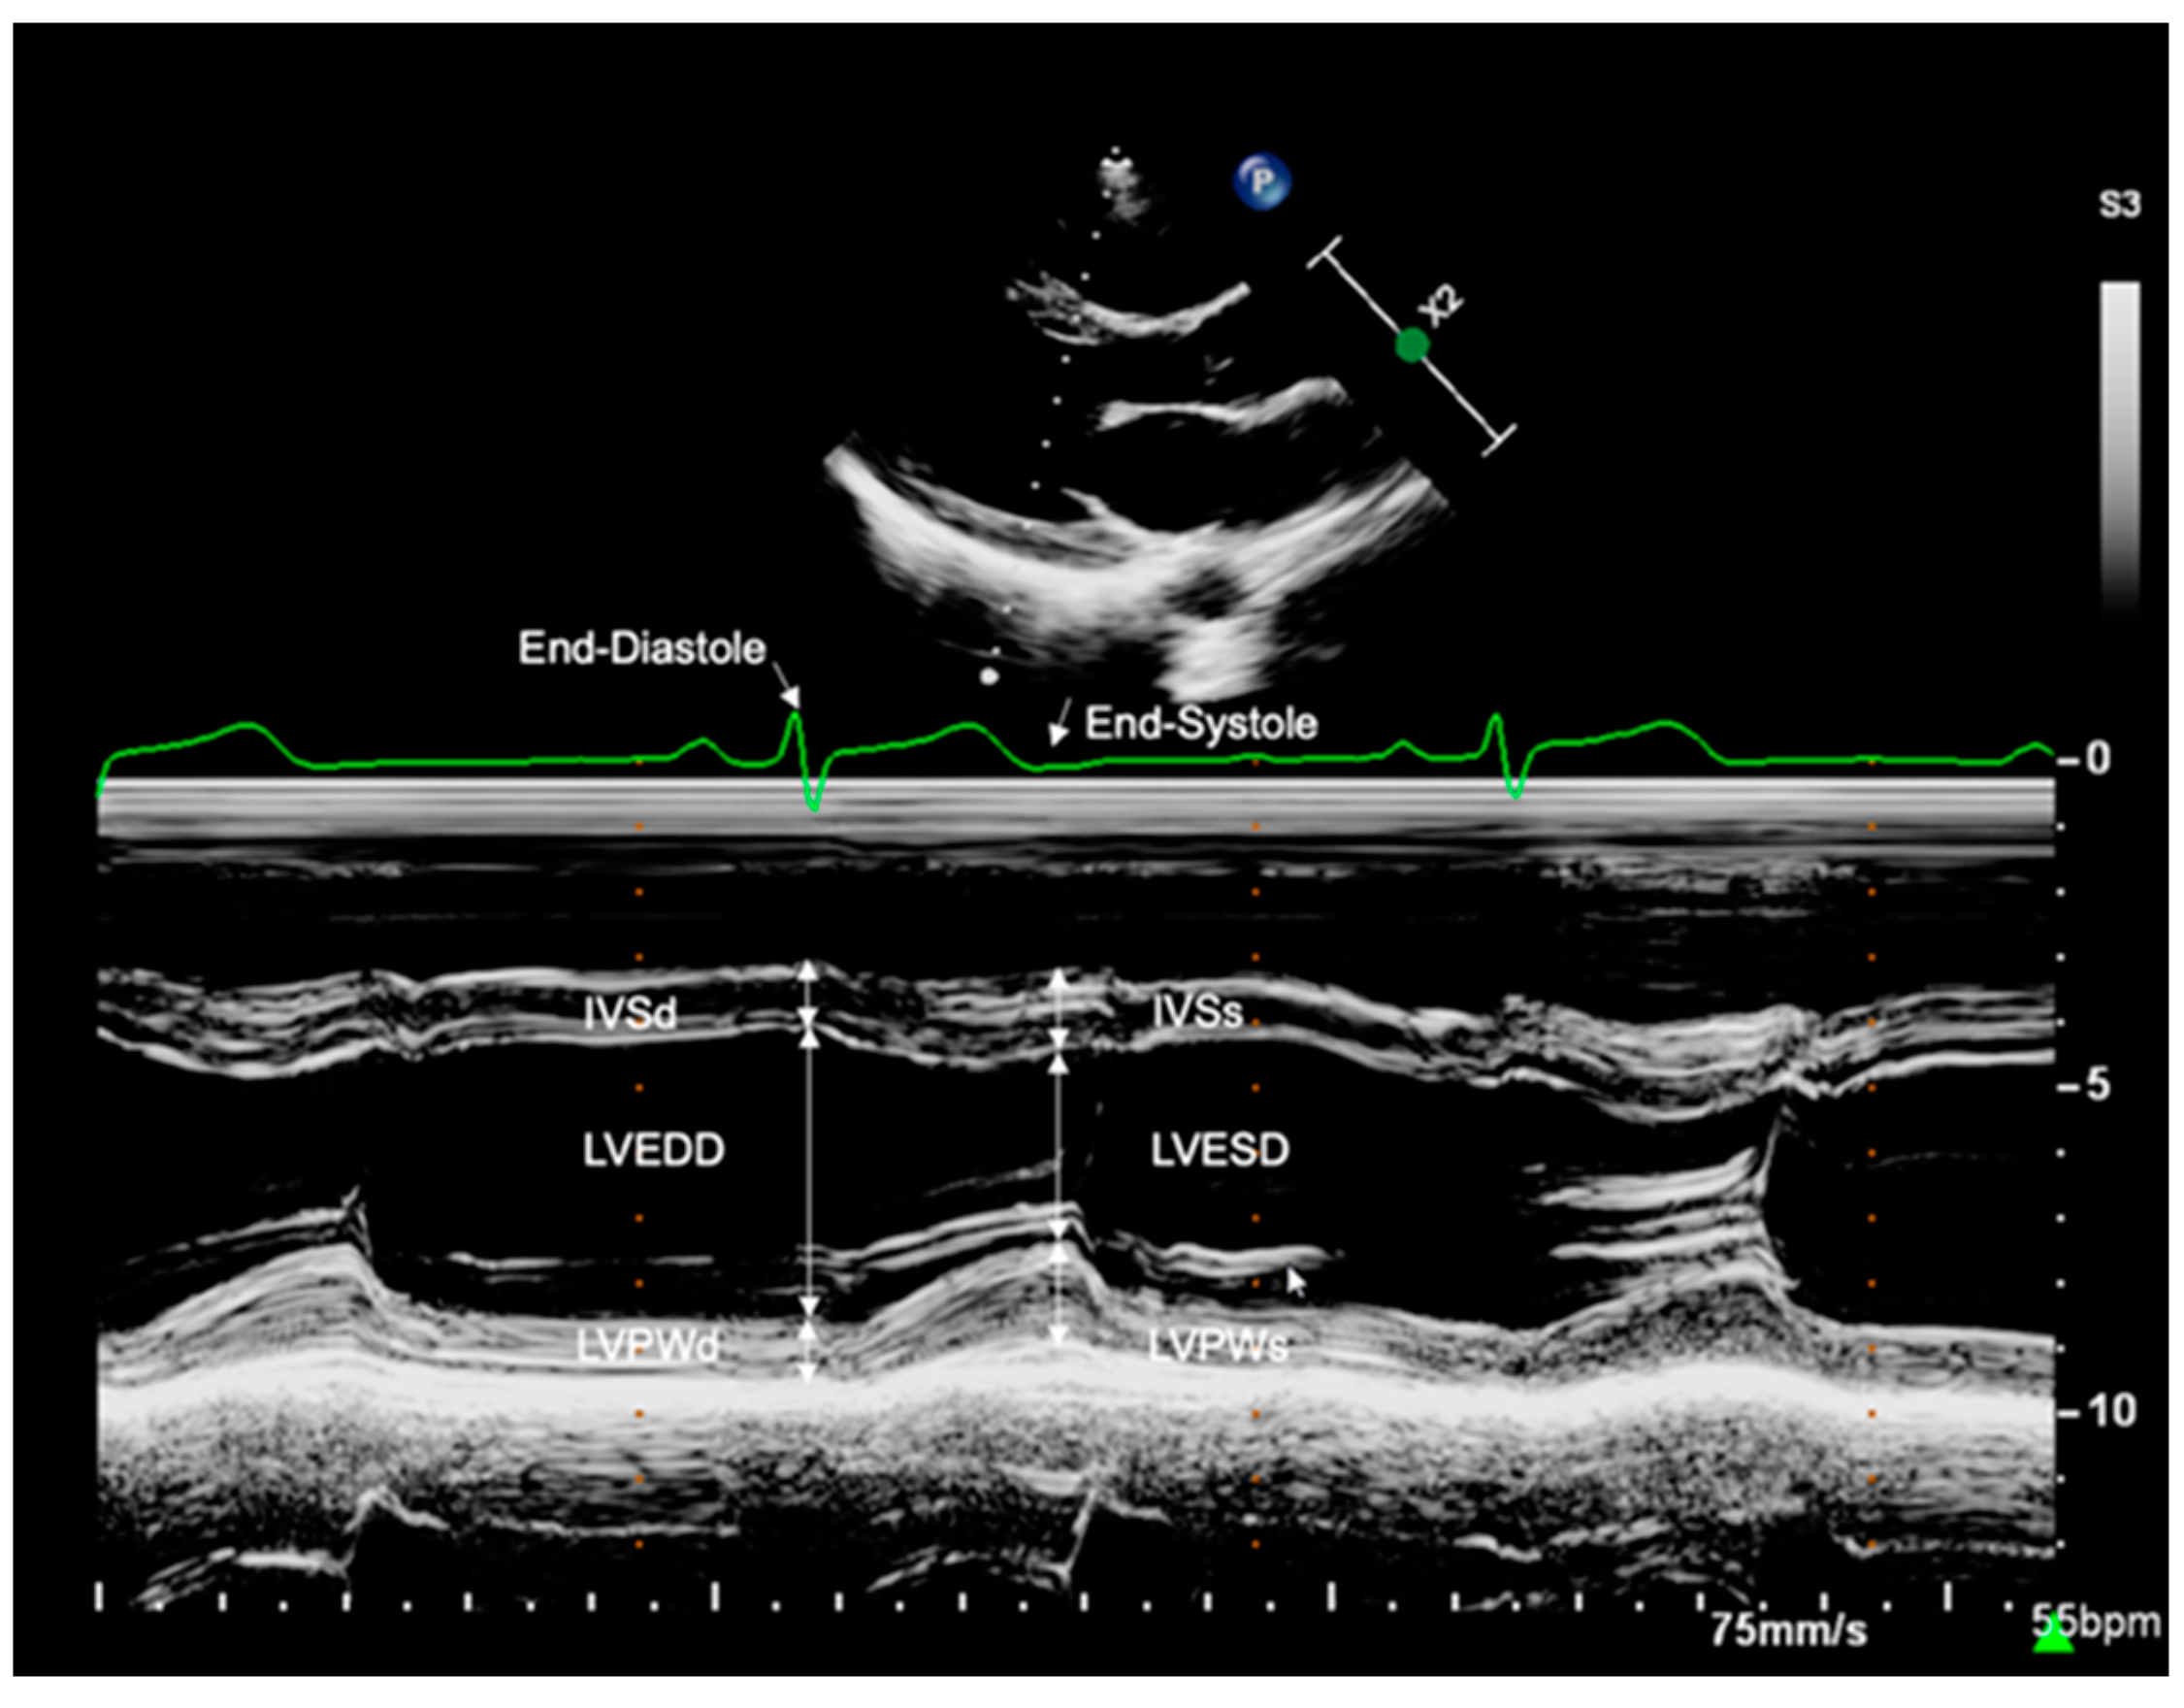

2.3.1. Left Ventricular Dimensions

| IVSd z-score | 0.21 ± 1.02 | 0.24 ± 1.02 | 0.857 | >0.999 |

| IVSs z-score | 0.32 ± 0.78 | 0.10 ± 0.94 | 0.179 | 0.774 |

| LVEDD z-score | −0.43 ± 1.01 | −0.34 ± 1.05 | 0.628 | >0.999 |

| LVESD z-score | −0.24 ± 0.90 | 0.03 ± 0.91 | 0.130 | >0.999 |

| LVPWd z-score | 0.27 ± 0.82 | 0.46 ± 0.82 | 0.226 | 0.327 |

| LVPWs z-score | −0.21 ± 0.95 | −0.49 ± 0.92 | 0.118 | 0.771 |

| IVSd (mm) | 9.45 (6.70–12.00) | 9.00 (7.30–10.00) | 0.218 | 0.761 |

| IVSs (mm) | 12.22 ± 1.80 | 12.04 ± 1.39 | 0.739 | 0.921 |

| LVEDD (mm) | 45.70 ± 4.11 | 44.41 ± 2.96 | 0.289 | 0.714 |

| LVESD (mm) | 30.00 (25.00–35.00) | 29.00 (26.00–34.00) | 0.469 | 0.500 |

| LVPWd (mm) | 8.70 (6.90–13.00) | 8.90 (7.40–11.00) | 0.551 | 0.824 |

| LVPWs (mm) | 12.50 (9.80–17.00) | 12.00 (9.80–16.00) | 0.468 | >0.999 |